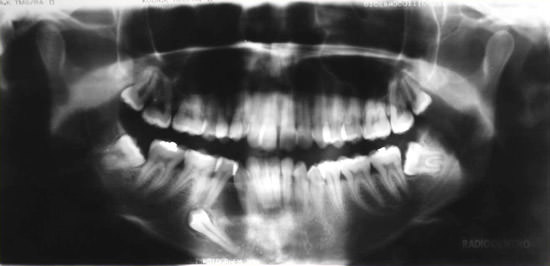

Paciente de 18 años, leucoderma, genero femenino, fue remitida por un ortodoncista al Servicio de Cirugía y Traumatología Buco-Maxilofacial del Hospital Universitario Oswaldo Cruz de la Universidad de Pernambuco (HUOC / UPE) con la finalidad de traccionar el diente incluido. Durante el análisis de la ortopantomografía (Fig. 01), se observó lesión radiolúcida de 03 cm de extensión adyacente al diente 44 retenido. La paciente no refería dolor a la palpación, pero fue evidenciado discreto aumento de volumen durante el examen físico (Fig. 3A). Fue realizada biopsia incisional asociada a punción aspirativa previa, que resulto negativa para sangre y/o material purulento. En seguida, la pieza fue enviada para análisis anatomopatológico.

Figura 1

Ortopantomografía mostrando lesión en cuerpo mandibular del lado izquierdo.

Radiográficamente, el fibroma ameloblástico se presenta en la mayoría de los casos como una zona radiolúcida multilocular con márgenes escleróticas. Normalmente presenta diámetro entre 1 a 8 cm. Tumores menores pueden tener imágenes uniloculares; lesiones mayores pueden romper las corticales óseas.(7) Frecuentemente el FA aparece asociado a un elemento dentario incluido.(1)